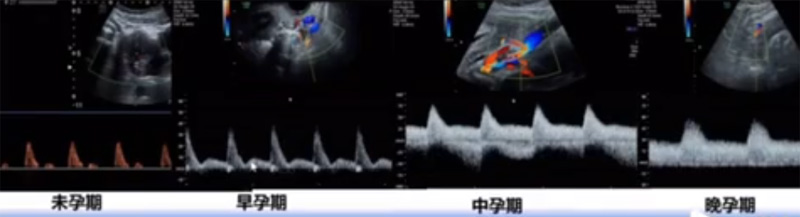

位于输卵管的后下方,子宫两侧的后上方;借卵巢系膜与子宫阔韧带后层相连。正常成人卵巢约4x3x2cm,跟睾丸的数值差不多,都是性器官,绝经后卵巢萎缩变小、变硬。所以绝经后妇女很难找到卵巢,主要功能:生殖和内分泌功能分泌性激素。女性的第二性征。女性内生殖器的血管分布,动脉有子宫动脉,卵巢动脉,阴道动脉,阴部内动脉。静脉它是与动脉伴行。重要了解的是子宫动脉,子宫动脉是髂内动脉前干的重要分支,妊娠时候血流速度会增加的,为无创性检查胎盘血管阻力的方法。未孕期频谱为高阻力低舒张波形;正常妊娠时血流速度增加,血流阻力下降。